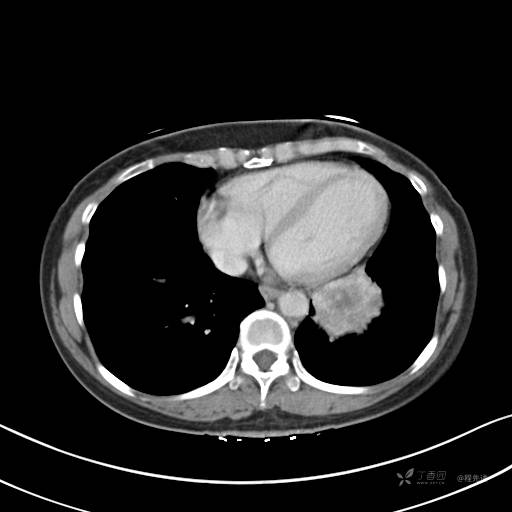

增强静脉期

静脉期CT值约84HU